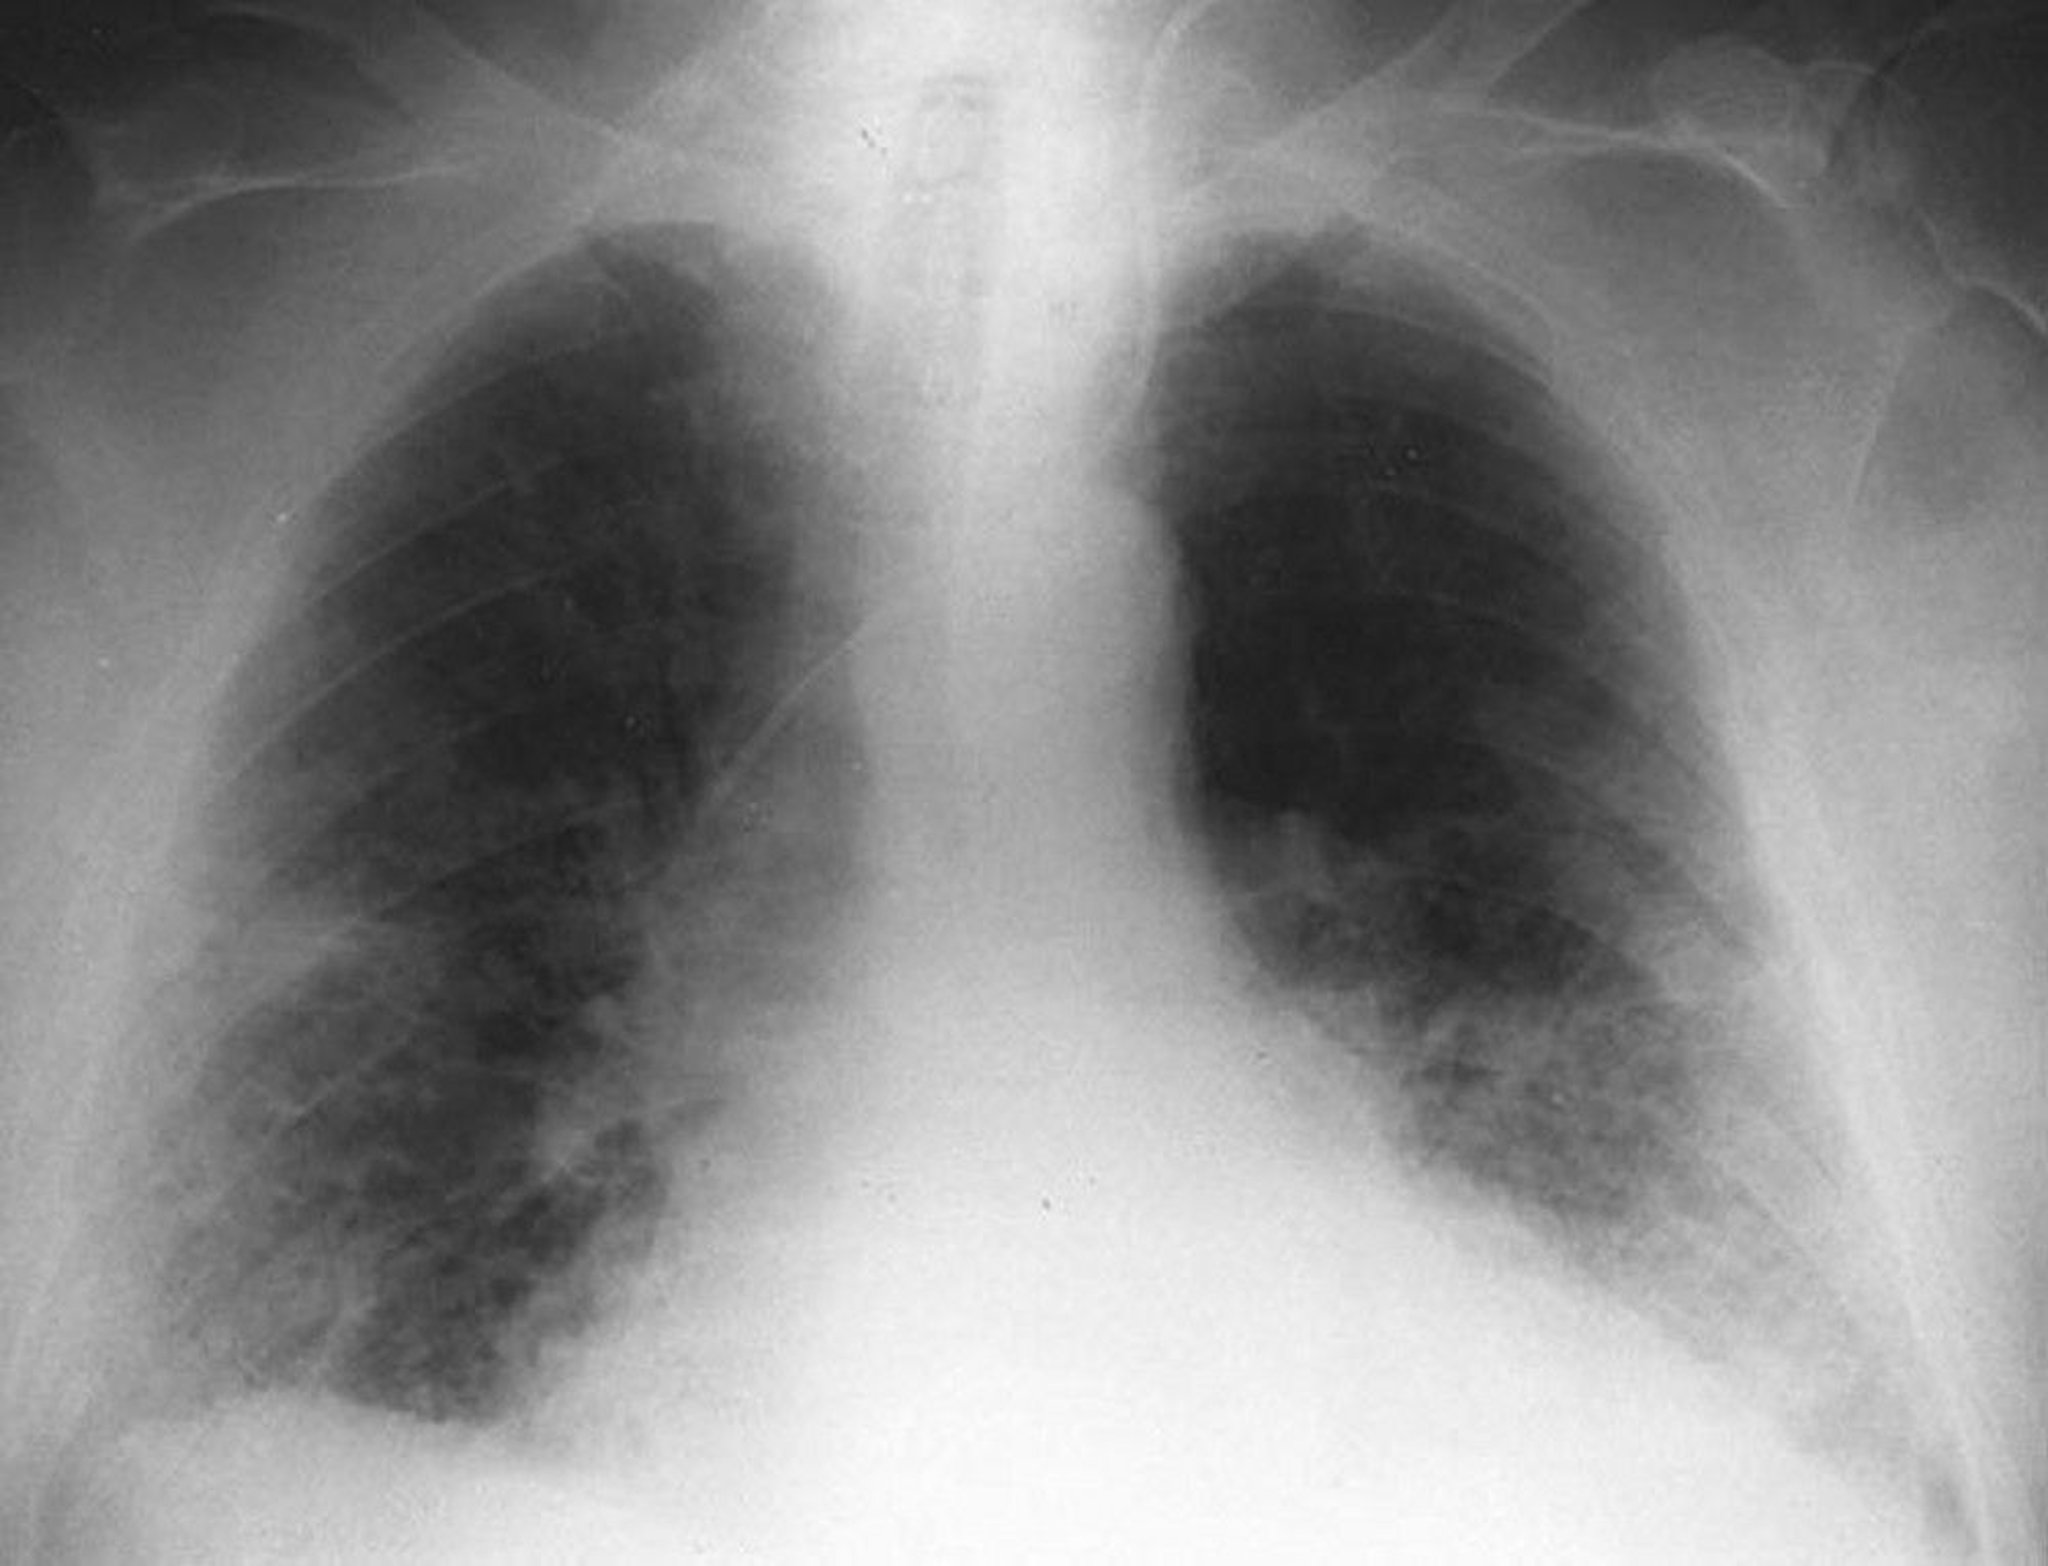

Bilateral interstitial opacities in an older male with respiratory syncytial virus pneumonia.

By permission of the publisher. From Betts R, Falsey A, Hall C, et al. In Atlas of Infectious Diseases: Pleuropulmonary and Bronchial Infections. Edited by GL Mandell (series editor) and MS Simberkoff. Philadelphia, Current Medicine, 1996.